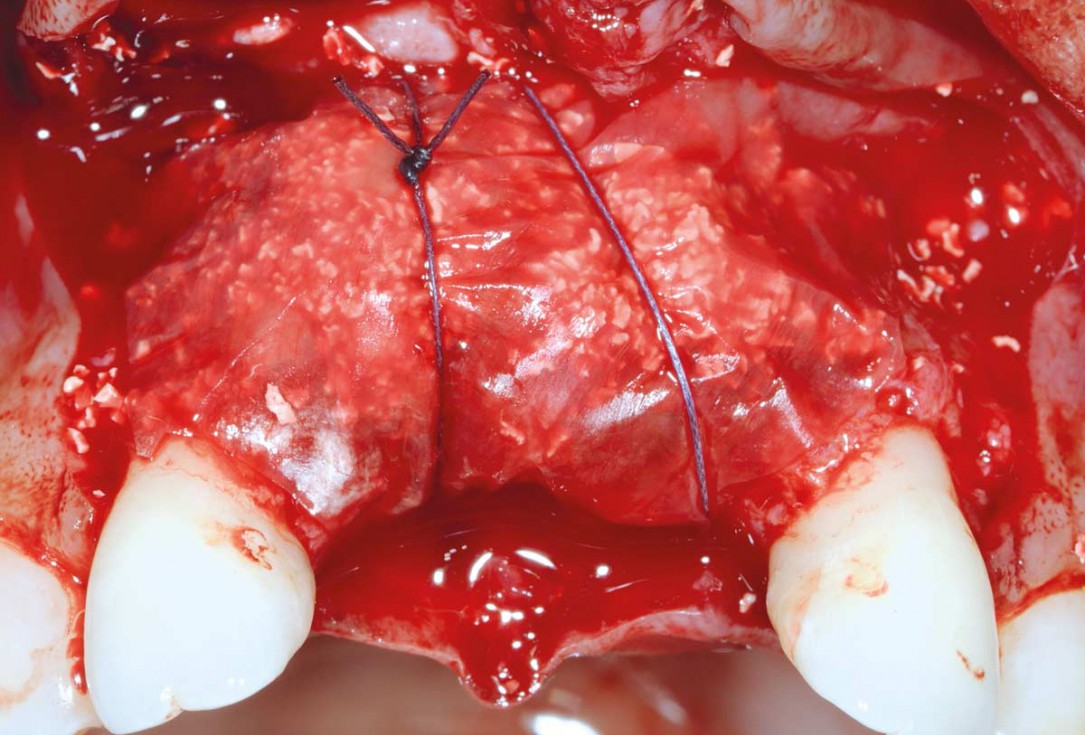

17/26 - Mattress sutures to stabilize the graftBone augmentation in aesthetic zone with maxgraft® bonering - Dr. A. Patel